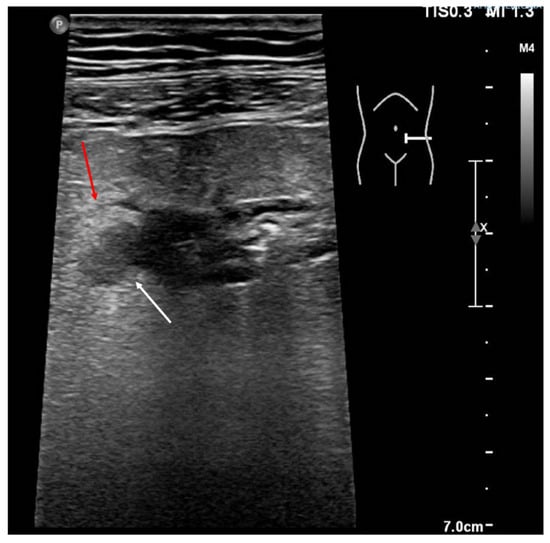

4. Acute Appendicitis